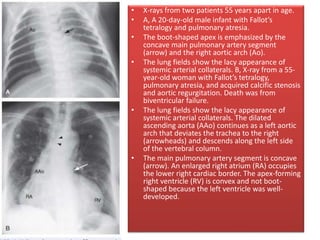

• X-rays from two patients 55 years apart in age.

• A, A 20-day-old male infant with Fallot’s

tetralogy and pulmonary atresia.

• The boot-shaped apex is emphasized by the

concave main pulmonary artery segment

(arrow) and the right aortic arch (Ao).

• The lung fields show the lacy appearance of

systemic arterial collaterals. B, X-ray from a 55-

year-old woman with Fallot’s tetralogy,

pulmonary atresia, and acquired calcific stenosis

and aortic regurgitation. Death was from

biventricular failure.

systemic arterial collaterals. The dilated

ascending aorta (AAo) continues as a left aortic

arch that deviates the trachea to the right

(arrowheads) and descends along the left side

of the vertebral column.

• The main pulmonary artery segment is concave

(arrow). An enlarged right atrium (RA) occupies

the lower right cardiac border. The apex-forming

right ventricle (RV) is convex and not boot-

shaped because the left ventricle was well-

developed.